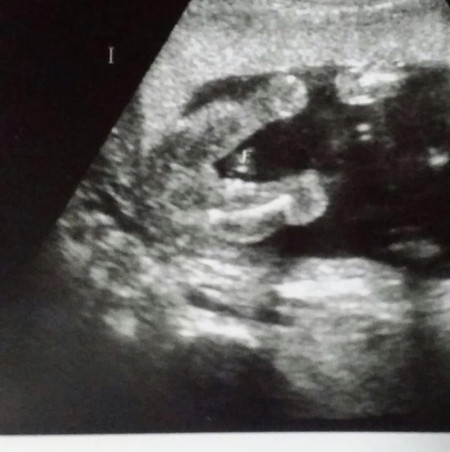

เพศลูก?

ลูกสาวใช่มั้ยคะแม่ๆ ช่วยคอนเฟริมหน่อยจ้า